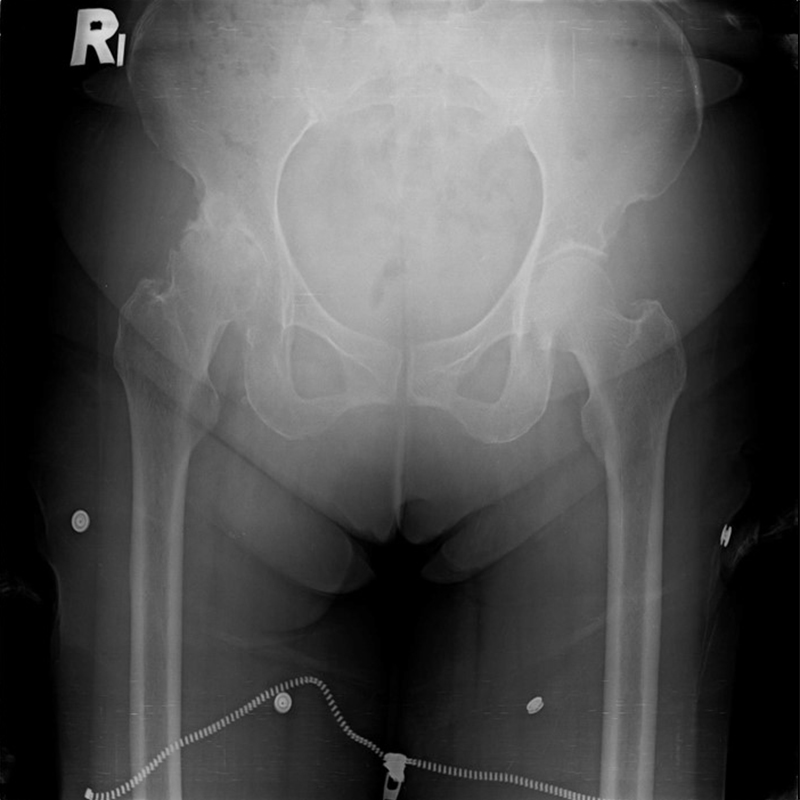

傳統髖關節置換 首頁 案例分享 髖關節手術 傳統髖關節置換 54歲蔡先生退化性關節炎 術前 術後 張女士 51歲 退化性關節炎(DDH先天發育不全 CROWE TYPE 2) 術前 術後 38歲林先生 退化性關節炎 術前 術後 72歲謝女士 退化性關節炎 術前 術後 71歲 謬女士 骨股頭壞死 術前 術後 50歲 郭先生骨股頭壞死 術前 術後 80歲 盧先生骨股頭壞死 術前 術後 林先生 37歲 術前 術後 邱女士 51歲 術前 術後 張女士 50歲 術前 術後